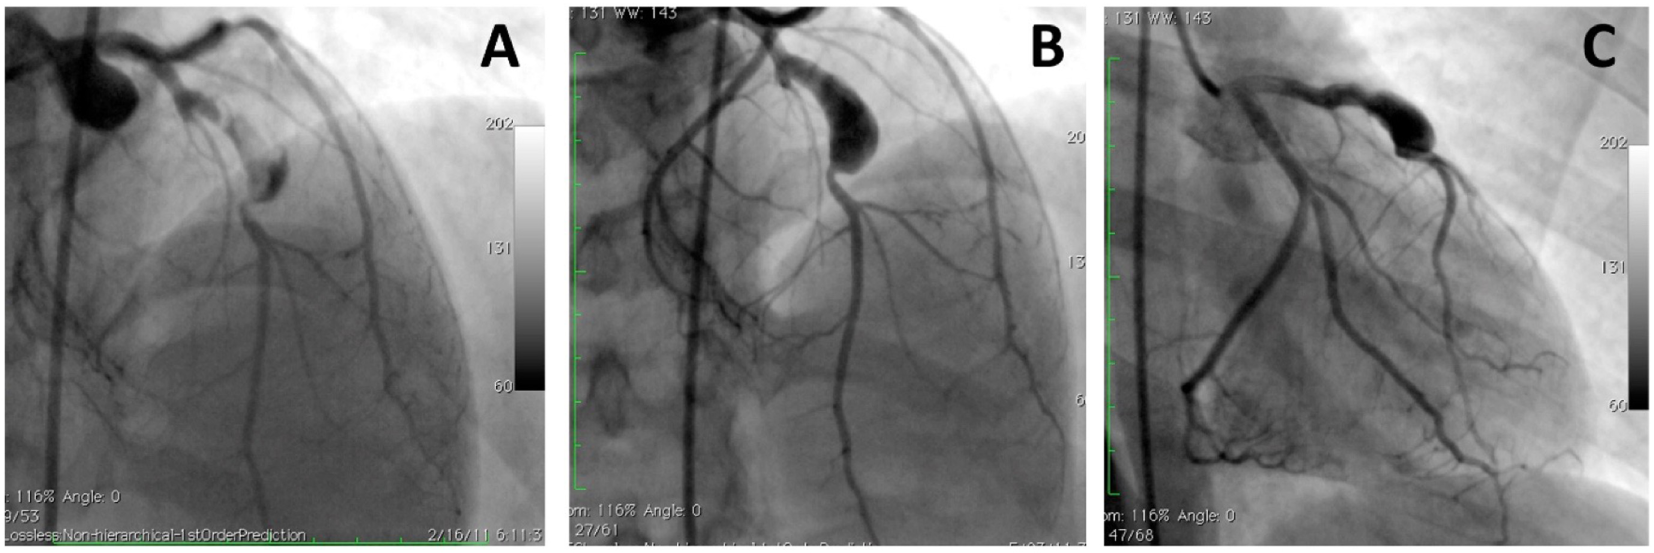

Figure 2

A large aneurysm in left anterior descending artery in a 17-year-old patient with neurofibromatosis causing acute coronary syndrome. Coronary angiograms with (A) and without (B,C) thrombus image in the aneurysm after anticoagulation. However, this patient was referred to surgery to prevent future complications [with permission from the report by Evrengul et al. (92)].